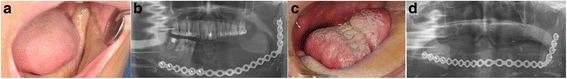

Eight patients were treated with retentive posts and prostheses. All patients underwent wide resections of the mandible, and reconstruction with an R-plate and microvascular soft tissue transfer. We adapted the retentive posts on an R-plate and fabricated the upper prostheses with a flexible denture or a fixed resin prosthesis. Finally, the patients had functional rehabilitation, which restored proper mastication.

8例患者接受了固位桩和修复体治疗。所有患者均接受了下颌骨的广泛切除,并采用R板和微血管软组织转移进行重建。我们在R板上适配了固位桩,并用可摘义齿或固定树脂修复体制备了上颌修复体。最后,患者实现了功能康复,恢复了正常咀嚼。